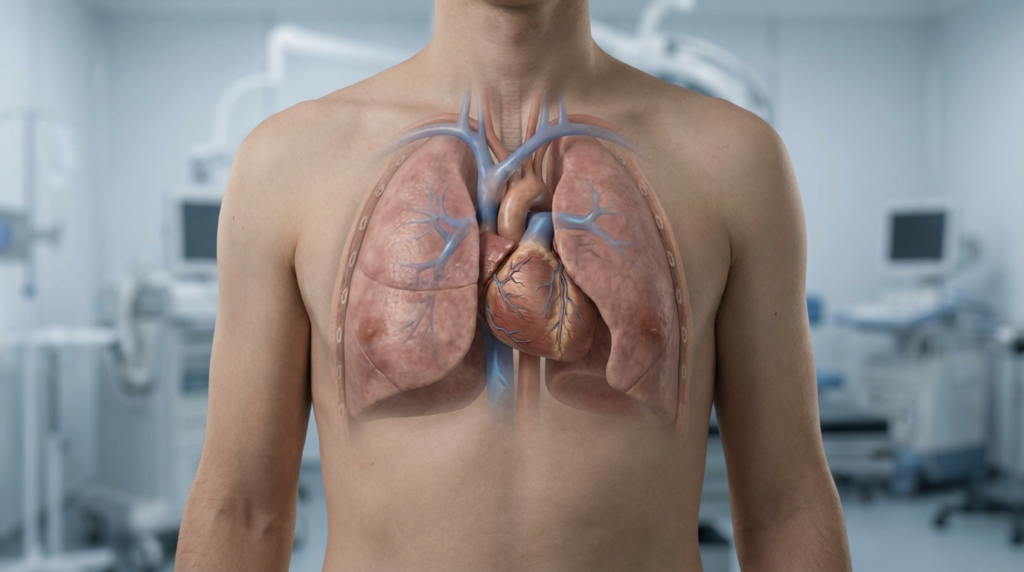

ما الذي يحدث داخل الجسم عند حبس النفس؟

عند حبس النفس، يبدأ الجسم تلقائيًا في تفعيل آلية فطرية تُعرف باسم استجابة الغوص. وهي استجابة بيولوجية طبيعية تظهر عند غمر الوجه في الماء البارد أو عند انخفاض إمداد الأكسجين، وتهدف أساسًا إلى حماية الأعضاء الحيوية.

تشمل هذه الاستجابة عدة تغيّرات أساسية، من أهمها:

- تباطؤ ضربات القلب لتقليل استهلاك الأكسجين.

- انقباض الأوعية الدموية الطرفية، مما يوجّه الدم نحو الأعضاء الأكثر أهمية مثل القلب والدماغ.

- زيادة قدرة الجسم على تحمّل ارتفاع ثاني أكسيد الكربون في الدم.

تساعد هذه التعديلات الفسيولوجية على إطالة مدة البقاء دون تنفّس، وتحدث بشكل لا إرادي حتى لدى الأشخاص غير المدرَّبين، وإن كانت تكون أكثر كفاءة لدى من يمارسون تمارين حبس النفس بانتظام.

تأثير حبس النفس على القلب والرئتين ومستوى الأكسجين

عند حبس النفس، ينخفض معدل ضربات القلب تدريجيًا، ما يؤدي إلى تقليل استهلاك الأكسجين داخل الجسم. وفي الوقت نفسه، يرتفع مستوى ثاني أكسيد الكربون في الدم، وهو ما يُعدّ عاملًا رئيسيًا في تنظيم التنفّس.

ومع التدريب المنتظم، يتعلّم الجسم كيف:

- يستخدم الأكسجين بكفاءة أعلى،

- يوزّع الدم بذكاء أكبر،

- ويتأقلم مع فترات قصيرة من نقص الأكسجين دون إجهاد مفرط.

هذا التكيّف التدريجي هو ما يسمح بزيادة مدة حبس النفس بأمان، دون تعريض القلب أو الرئتين لضغط غير صحي.

دور ثاني أكسيد الكربون في التحكم بالتنفس

يلعب ثاني أكسيد الكربون دورًا محوريًا في عملية التنفّس. فالإحساس بالحاجة إلى الشهيق لا ينتج أساسًا عن نقص الأكسجين، بل عن ارتفاع مستوى ثاني أكسيد الكربون في الدم.

ومع التدرّب الصحيح، يمكن تحسين تحمّل هذا الارتفاع بشكل آمن، مما يساعد على تأخير الإحساس بالانزعاج والرغبة في التنفّس.

ومع ذلك، من الضروري التأكيد على أن هذا التحكّم يجب أن يتم ضمن حدود آمنة ومدروسة، دون إجبار أو تجاهل لإشارات الجسم التحذيرية.